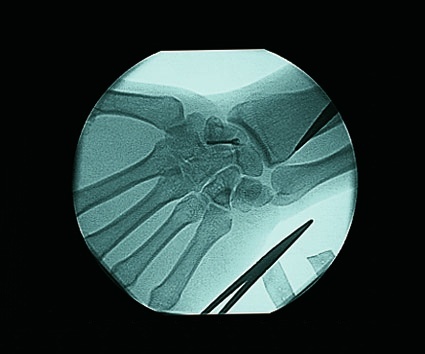

Clinical & System Images